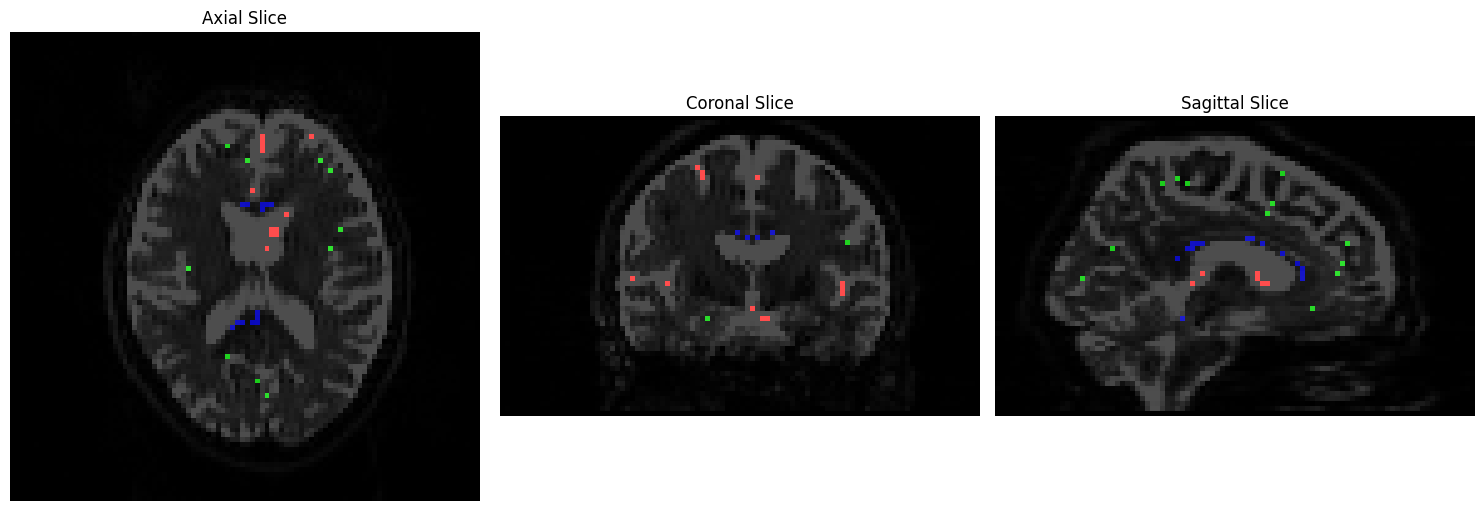

The next argument specifies your input data, and the resulting response functions for the different tissue types. The order matters; you can call the output files whatever you want, but it makes the most sense to label them as some kind of variation on the phrases “white matter”, “grey matter”, and “cerebrospinal fluid” (here, labeled as “wm.txt”, “gm.txt”, and “csf.txt”). The last option, “-voxels”, specifies an output dataset that shows which voxels from the image were used to construct the basis functions for each tissue type. This dataset can be viewed by typing the following:

We will visualize the voxels used to construct a basis function for each tissue type using Matplotlib. CSF voxels should be colored red, gray matter voxels green, and white matter voxels blue:

# Plot the slices using Matplotlib

fig, axes = plt.subplots(1, 3, figsize=(15, 5))

# Axial slice

axes[0].imshow(np.rot90(data1[:, :, slice_idx1, 0]), cmap="Greys_r", vmin=0, vmax=700)

axes[0].imshow(np.rot90(rgb_overlay[:, :, slice_idx1]), alpha=0.7)

axes[0].axis("off")

axes[0].set_title('Axial Slice')

# Coronal slice

axes[1].imshow(np.rot90(data1[:, slice_idx2, :, 0]), cmap="Greys_r", vmin=0, vmax=700)

axes[1].imshow(np.rot90(rgb_overlay[:, slice_idx2, :]), alpha=0.7)

axes[1].axis("off")

axes[1].set_title('Coronal Slice')

# Sagittal slice

axes[2].imshow(np.rot90(data1[slice_idx3, :, :, 0]), cmap="Greys_r", vmin=0, vmax=700)

axes[2].imshow(np.rot90(rgb_overlay[slice_idx3, :, :]), alpha=0.7)

axes[2].axis("off")

axes[2].set_title('Sagittal Slice')

# Adjust layout and display

plt.tight_layout()

plt.show()